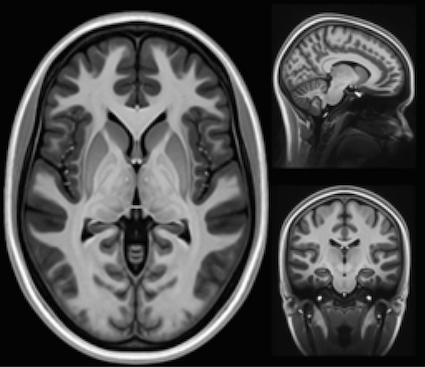

D’abord, parce qu’on diagnostique mieux. Avant, beaucoup de patients étaient classés dans d’autres maladies neurologiques. Aujourd’hui, avec l’imagerie, les critères médicaux plus précis et la vigilance accrue, on identifie davantage de cas. Donc mécaniquement, les chiffres montent.